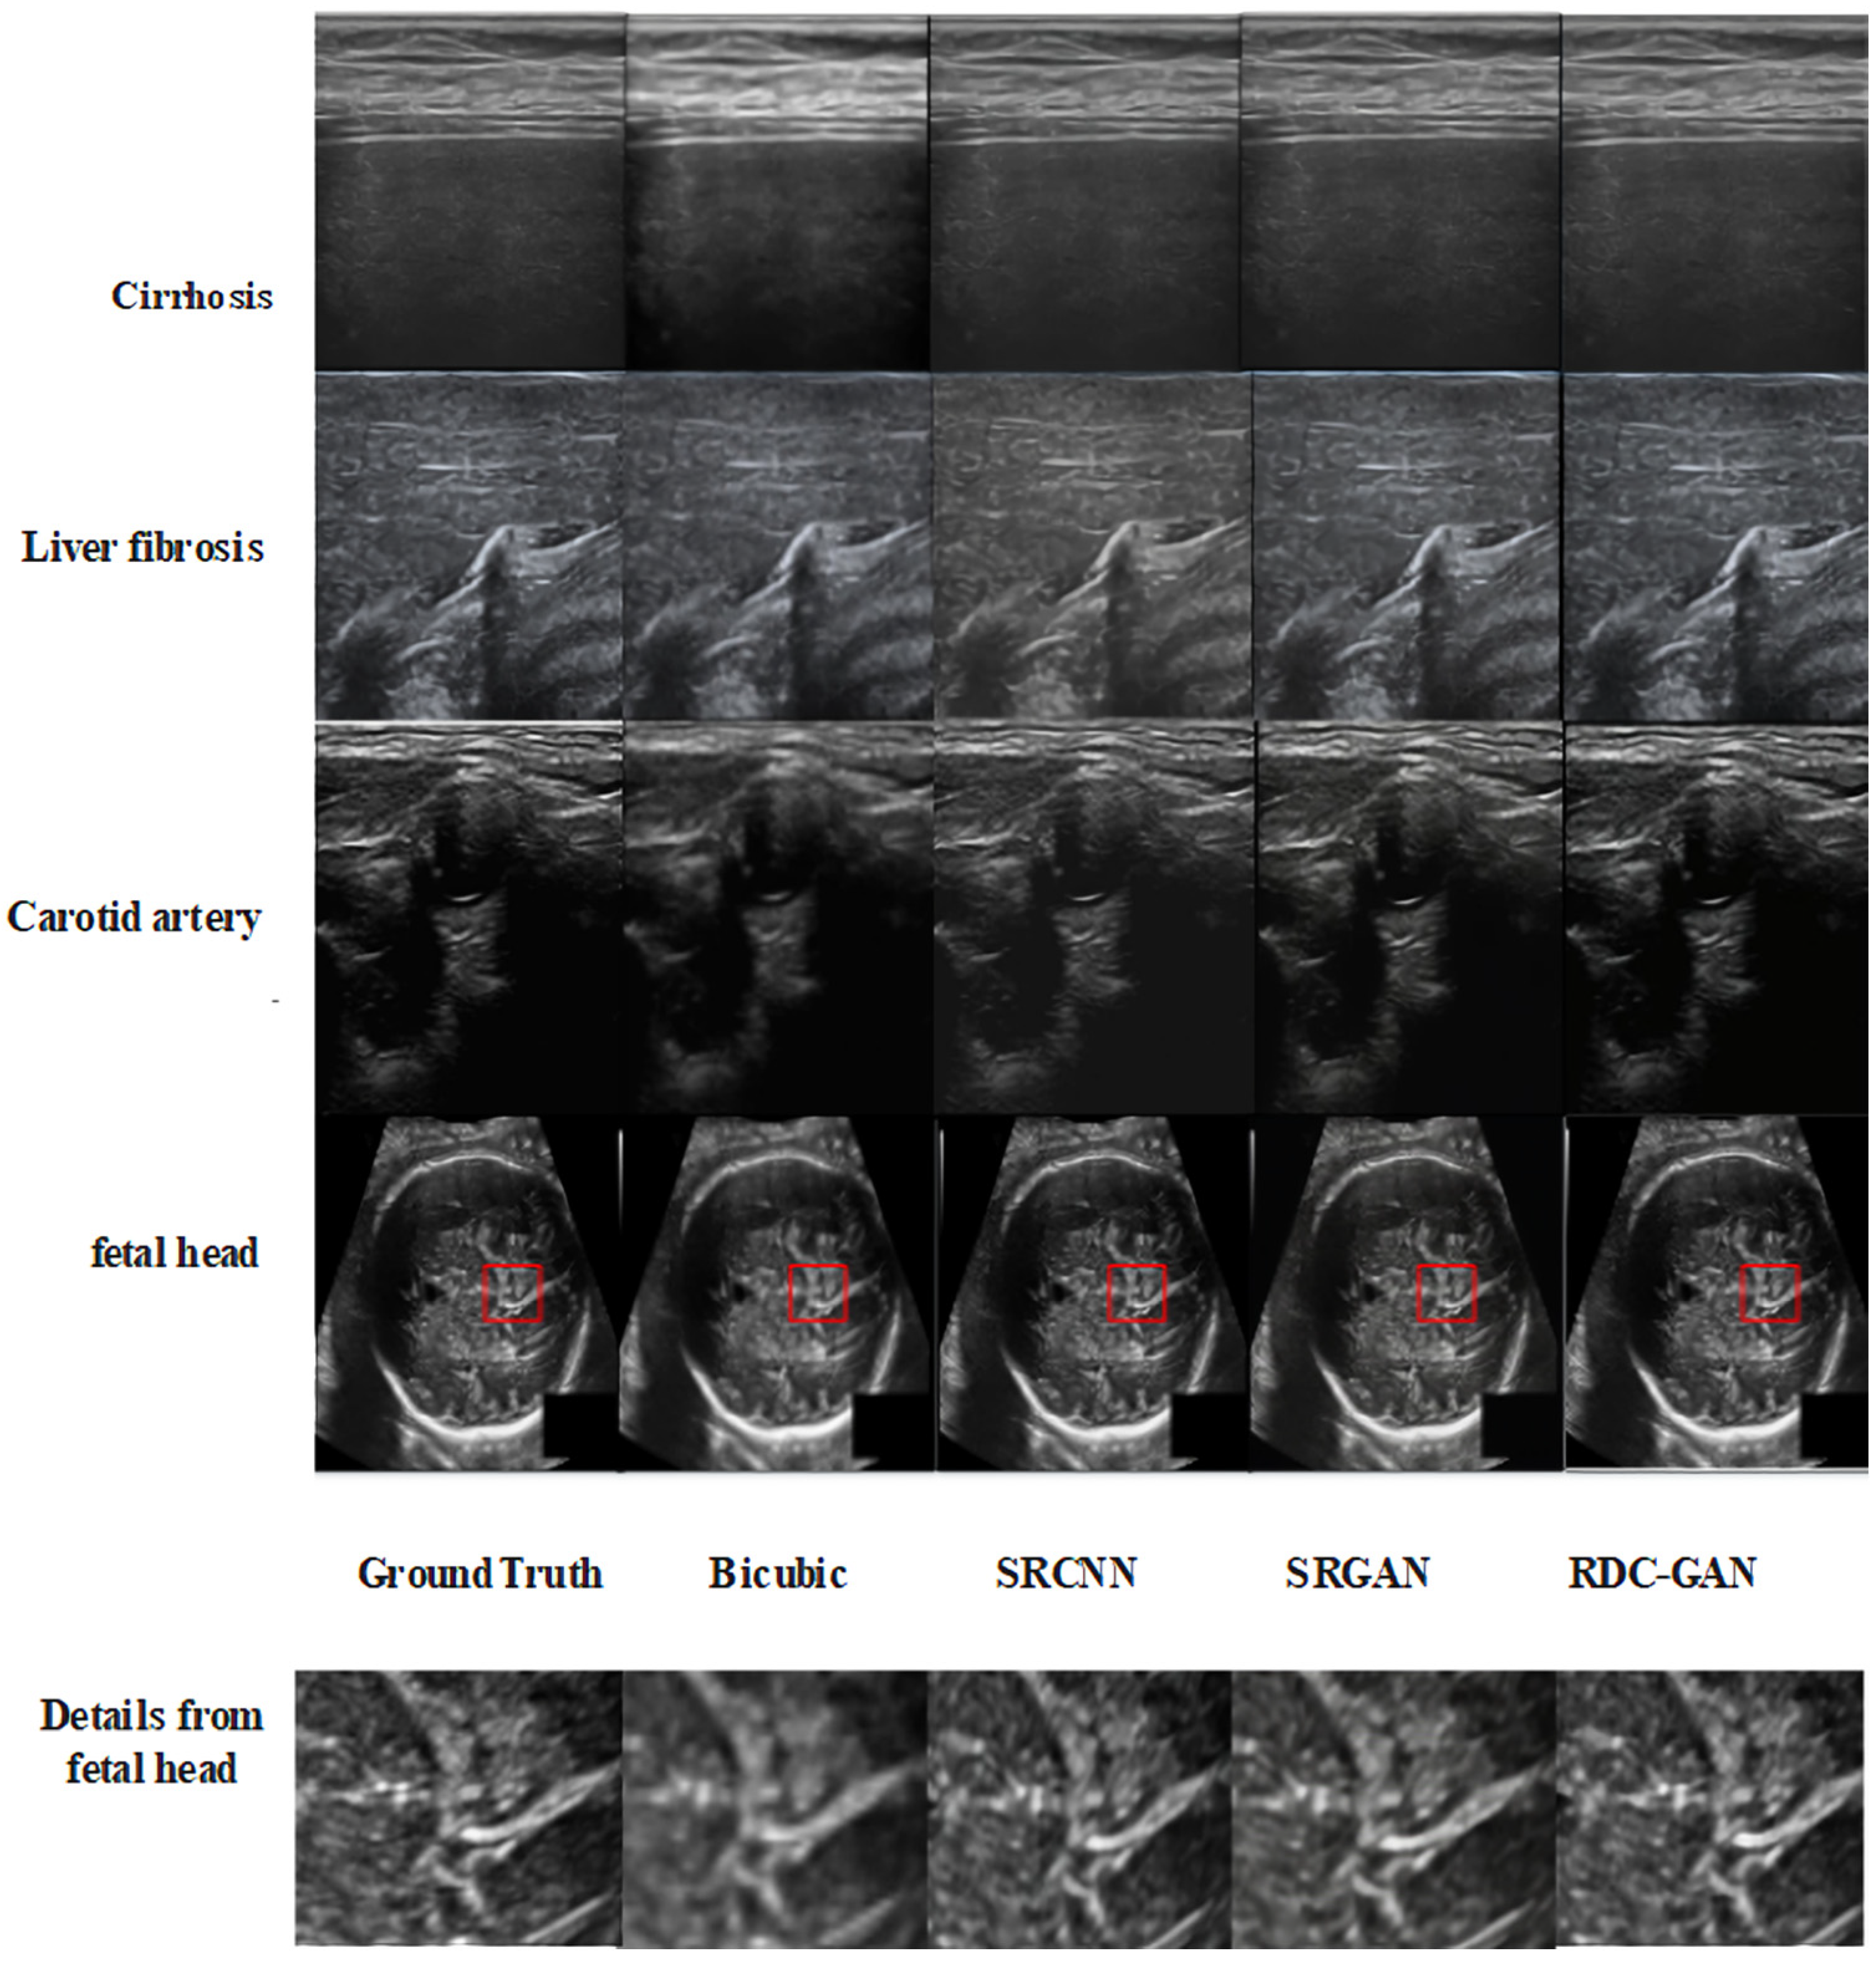

4.2. Qualitative Analysis